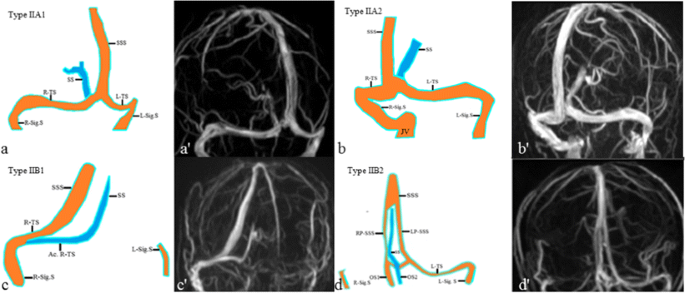

Figure 2 From Evaluation Of Dural Venous Sinuses And Confluence Of Sinuses Via Mri Venography Anatomy Anatomic Variations And The Classification Of Variations Semantic Scholar

Evaluation Of Dural Venous Sinuses And Confluence Of Sinuses Via Mri Venography Anatomy Anatomic Variations And The Classification Of Variations Springerlink